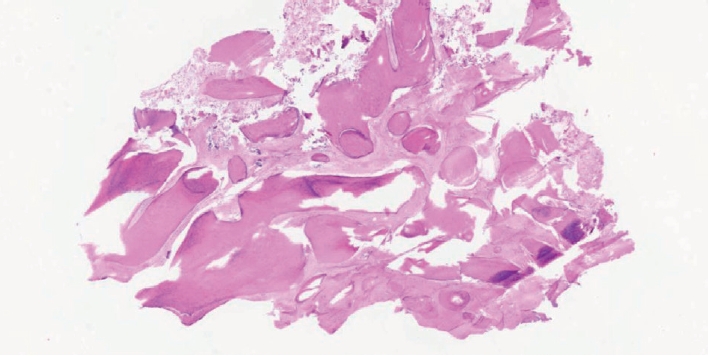

증 례26세 여성이 좌측 후이개 부위의 촉지 가능한 종괴를 주소로 내원하였다. 환자는 과거력상 선천성 심방중격결손이 있었고, 가족력으로는 모친이 유방암을 진단받은 병력이 있었으며, 약물 복용력은 없었다. 병력 청취상 해당 병변은 약 2년 전부터 만져졌으며, 점차 크기가 증가하였고 간헐적인 통증을 호소하였다. 이통 설문지상 시각통증척도(visual analog scale)는 3점으로 찌르는 듯한 양상의 통증이 수분 이내에 자연 완화된다고 하였다. 청력 저하, 이루, 어지럼증 등 기타 이과적 증상은 동반되지 않았다. 신체 진찰에서 좌측 후이개 부위에 약 26×22 mm 크기의 단단한 고형성 종괴가 촉지되었고(Fig. 1), 측두골 전산화단층촬영(CT)상 좌측 유양돌기에 약 16×8 mm 크기의 원형(round) 병변이 관찰되었으며, 주변 피질골과 유사한 밀도의 소견으로 연조직성 병변보다는 골성 병변을 의심할 수 있었다. 병변은 경계가 비교적 명확하고 유양동 피질골과 구분되는(isolated) 형태를 보여, 이러한 영상 소견에 따라 골종(osteoma)이 먼저 의심되었다(Fig. 2). 정확한 진단을 위하여 국소마취 하 절제 생검술(excisional biopsy)을 시행하였다. 병변을 중심으로 12시에서 7시 방향으로 절개를 가하고 박리하였다. 수술 소견상 병변은 단단하고 비교적 잘 박리되는 골성 종괴로, 종괴와 정상골의 경계가 비교적 명확하였으며, 측두골과 단단히 유착되어 있지는 않았다(Fig. 3A). 드릴과 가우지를 이용하여, 정상 피질골(cortical bone)이 명확히 노출될 때까지 제거하였다(Fig. 3B). 출혈 여부를 확인한 후 봉합 및 압박 드레싱을 시행하고 수술을 종료하였다. 병리조직검사 결과, 섬유성 기질(fibrous stroma) 내에 무질서하게 배열된 조직골(woven bone)이 관찰되어 단일병소형 섬유성 이형성증(monostotic fibrous dysplasia)으로 최종 진단되었다(Fig. 4). 수술 후 2개월째 수술 부위는 특별한 합병증 없이 회복되었으며(Fig. 5), 현재 수술 후 1년까지 추적 관찰한 결과 재발 소견 없이 외래에서 경과 관찰 중이다.

측두골에 발생한 FD는 병변의 위치와 범위에 따라 외이도 협착, 전도성 난청, 진주종성 중이염 등의 다양한 증상을 동반할 수 있다[9]. 기존 보고에 따르면, 측두골 FD 환자의 약 60%-70%는 청각 증상을 동반하며[10], Frisch 등[8]은 66예의 분석에서 73%에서 두통, 난청, 어지럼 등의 증상을 보고하였다. 그러나 본 증례와 같이 청각 증상 없이 후이개 부위의 종물로만 발견되는 경우는 매우 드물며, 림프절병증, 피지낭종(epidermoid cyst), 지방종(lipoma) 등의 연부조직 종물과 감별이 필요하다[11,12]. 골성 병변으로는 골종(osteoma), 골아세포종(osteoblastoma), FD 등이 감별진단에 포함될 수 있다[13]. 영상학적으로 FD는 CT에서 ground-glass appearance가 특징적이나[14], 균일한 고밀도 병변 또는 낭성 병변처럼 보이는 경우도 있어, 감별이 어려울 수 있다. 따라서 영상 소견이 불명확한 경우에는 병리조직검사를 통한 확진이 필요하다. 병리조직학적으로는 섬유성 기질 내 무질서한 조직골(woven bone) 배열이 특징이며, 일반적으로 골아세포나 파골세포는 관찰되지 않는다[6]. 감별해야 할 병변으로는 골종, 골아세포종, 골육종 등이 있는데, 골종은 성숙한 층판골(lamellar bone)로 이루어져 있고, 골아세포종은 조직골이 섬유혈관성 기질 내에서 형성되며 가장자리에 뚜렷한 골아세포층이 관찰된다[13,14]. 본 증례는 섬유성 기질 속에 무질서한 조직골이 보였으나, 골아세포층이나 골육종의 침습적 소견은 없었고, 골종의 성숙한 층판골 소견과도 달라 섬유이형성증으로 확진할 수 있었다.

NotesAuthor Contribution Conceptualization: Se-Joon Oh. Data curation: Han-Seul Na, Kyung Un Choi. Formal analysis: Han-Seul Na, Kyung Un Choi. Investigation: Se-Joon Oh. Methodology: Se-Joon Oh, Project administration: Se-Joon Oh. Supervision: Se-Joon Oh. Visualization: Han- Seul Na, Kyung Un Choi. Writing—original draft: Han-Seul Na. Writing—review & editing: Han-Seul Na, Se-Joon Oh. Fig. 1.Preoperative clinical finding of the left retroauricular mass. A firm, immobile subcutaneous mass measuring approximately 26×22 mm was observed in the left retroauricular region. The overlying skin was intact, without signs of inflammation or discoloration. Fig. 2.Preoperative CT scans showing a dense bony lesion on the left temporal bone. A: Axial view demonstrates a well-defined hyperdense mass on the outer table of the mastoid bone. B: Coronal view shows the lesion’s limited extent without involvement of the inner table. Fig. 3.Intraoperative findings. A: The excised bony mass measuring approximately 2 cm in diameter. B: Surgical field after complete excision of the lesion, revealing exposed cortical bone. REFERENCES2. Pontes-Madruga TC, Filgueiras HVC, Silva DMSD, Silva LSD, Testa JRG. Fibrous dysplasia: rare manifestation in the temporal bone. Braz J Otorhinolaryngol 2022;88(2):235-42.